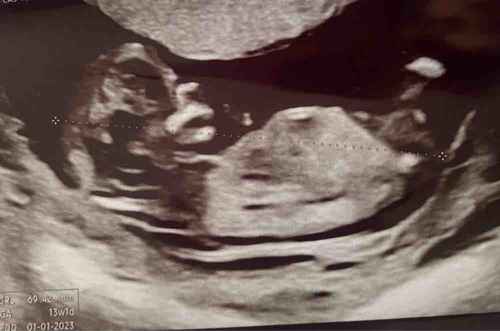

Iemand die een gokje durft te wagen?🥰

Ik gok jongen in wording

Hoever ben je hier?

Blauw: omranding

Rood: Blaas

Groen: stand nub en blaas met ruggengraad

Zoals je kan zien in de ingezoomde echos met alleen blauw zie je een klein bolletje/boven de nub lijn. Dit is normaal het begin van de ontwikkeling van de pipi

De lijn van de nub veranderd dan in de balletjes.

Zoals op de echo met de andere kleuren lijnen is er meer schaduw bij gedaan waardoor je ook duidelijker ziet dat de nub omhoog staat. De blaas zit ook erg laag en van nub naar blaas naar ruggengraad staat het in een hoek naar de ruggengraad(📐) dit duidt op een jongen. Bij meisjes loopt het gelijk of bijna gelijk aan de ruggengraad(=) de blaas zit daar dichter tegen de nub aan en is de nub plat en is er geen bolletje.

Dus ik gok jongen

Bedankt voor de uitgebreide uitleg.👌🏻 Ik ben 13+6.

Moet wel zeggen dat ik wel wat meer had verwacht met dat termijn. Vaak zie je dan al echt pipi en balletjes omhoog staan. Maar kan ook liggen aan hoe ze de echo gemaakt hebben. Bij een meisje met dit termijn moest het zowiezo plat zijn. Dus denk dat ze expres de echo wat minder duidelijk(donkerder) hebben gehouden bij de nub heb ik wel wat vaker gemerkt.

Maar door alle duideljke dingen gok ik toch echt jongen. Laat je het nog even weten als je het weet?

Erg lastig. Vaak verwacht ik wat meer te zien maar lijkt of met de 13 weken echo ze expres de nub wat minder goed op beeld zetten. Op het moment gok ik toch jongen. Door het bolletje erboven en de blaas die lager ligt. Je had niet nog een echo?